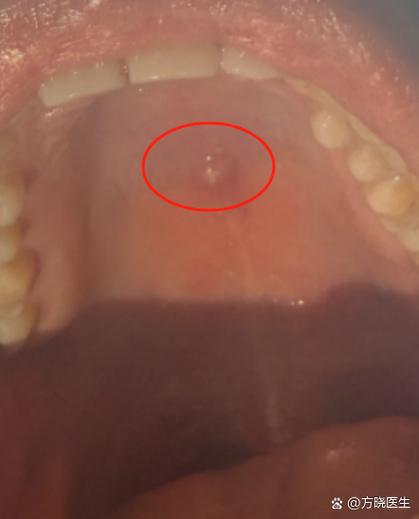

口腔内肉眼可见的病理表现

如果阻生牙部分萌出,可能会在口腔后部牙龈上看到一些异常表现。

肉眼可见的特征:

- 牙龈肿包/脓包: 这是冠周炎的典型表现,部分萌出的牙齿和牙龈之间会形成一个盲袋,食物残渣和细菌容易堆积,难以清洁,当身体抵抗力下降时,就会引发急性炎症,导致牙龈红肿、疼痛,甚至形成脓包,可能伴有口臭、张口受限、发烧等症状。

- 牙龈增生: 长期的慢性刺激可能导致牙龈组织过度增生,覆盖在部分牙冠上,形成一个“小帽子”。

- 牙齿形态异常: 有时萌出部分可能很小,或者形态不正常。